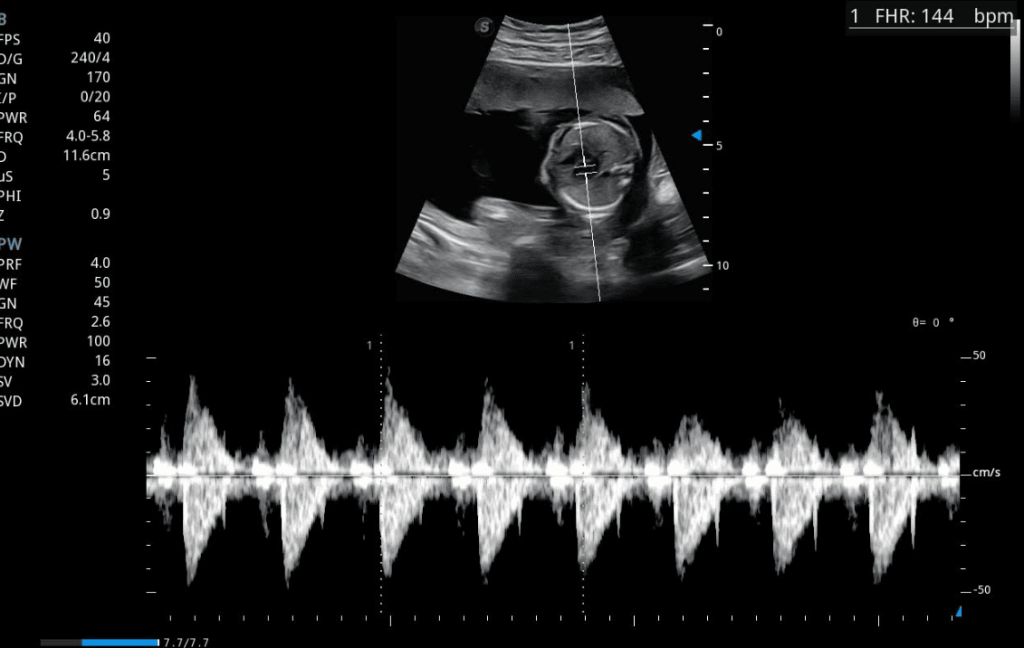

Doppler del ductus venoso fetal con espectro de ondas S, D y a para evaluar función cardiovascular y bienestar fetal

En condiciones normales, el flujo dentro del ductus venoso es continuo y dirigido hacia el corazón fetal durante todo el ciclo cardíaco. En el gráfico espectral, este flujo se representa con tres ondas principales: S, D y a.

• La onda S refleja la contracción ventricular.

• La onda D corresponde al llenado pasivo del ventrículo.

• La onda a representa la contracción auricular.

Si esta última onda (onda a) se observa ausente o invertida, puede ser un signo temprano de sobrecarga cardíaca, hipoxia, o anomalías estructurales del corazón. Por ello, la evaluación del ductus venoso tiene un valor predictivo crucial en el diagnóstico prenatal avanzado.